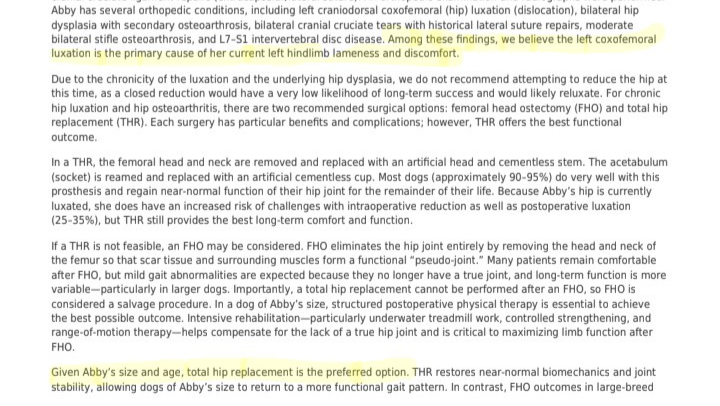

Abby's lifelong struggle with joint pain, from the trauma she's endured, began manifesting dramatically a few years ago when she tore both of her CCLs (cruciate ligaments), a year apart, requiring two separate surgeries. Unfortunately, the second surgery was not successful, leaving her with chronic instability. To manage the resulting pain, her medication regimen has gradually increased until she recently reached the maximum safe pain regimen her vet is comfortable giving her including Gabapentin, Galliprant, Librela, and Amantadine while she also receives treatment for her anxiety and hypothyroidism (a condition that contributed to her weight, which her vet and I are managing with medication and diet changes). The Need Abby's hip joint has suffered a Cranial Dorsal Luxation (a severe dislocation), meaning the top of her femur is grinding painfully on top of the hip socket.

Because her current, maxed-out medication cocktail is still not enough to control this relentless pain, the specialists at OSU Veterinary College have determined that this luxation cannot be fixed by any other means than definitive surgery.

Our options are either an FHO (where they cut off the head of the femur and allow scar tissue to become a floating joint) or the preferred, yet costly, Total Hip Replacement (THR). The FHO isn't reccomend for dogs over 70lbs. Even when Abby loses more weight, she'll never be that light.